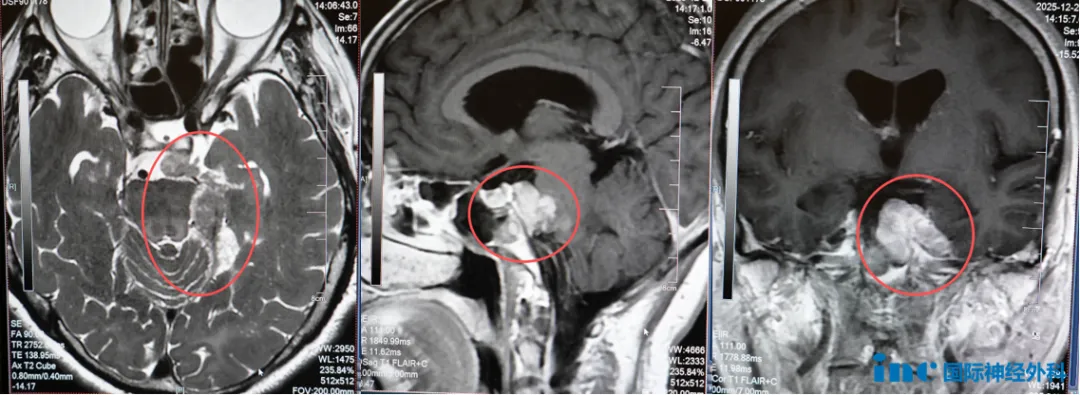

手术台上,61岁的鲁女士已与脑膜瘤缠斗23年。2003年首次开颅手术后,肿瘤残留引发的症状迫使她接受了伽马刀治疗;2012年肿瘤复发,她进行了第二次伽马刀治疗。然而,谁能想到,一场漫长“车轮战”后,这个良性的肿瘤竟然再度卷土重来,且更为复杂难缠。2018年以来,鲁女士逐渐出现左侧耳鸣、左侧面部持续性麻木疼痛以及面瘫等。

“伽马刀治疗后形成的粘连让手术难度倍增。”巴教授在术前分析中指出,鲁女士的肿瘤已呈多灶性分布,一个病灶位于幕下,一个朝向颞叶生长,还有部分病灶压迫脑干,同时累及三叉神经走行区域——这正是症状的根源。

这种情况下的手术,犹如在错综复杂的荆棘丛中穿行,稍有不慎就可能造成不可逆的神经损伤。

正常解剖结构难以辨析,加之此前开颅手术已改变局部解剖关系,术区出现的瘢痕和组织粘连,更让辨认肿瘤边界变得异常困难。